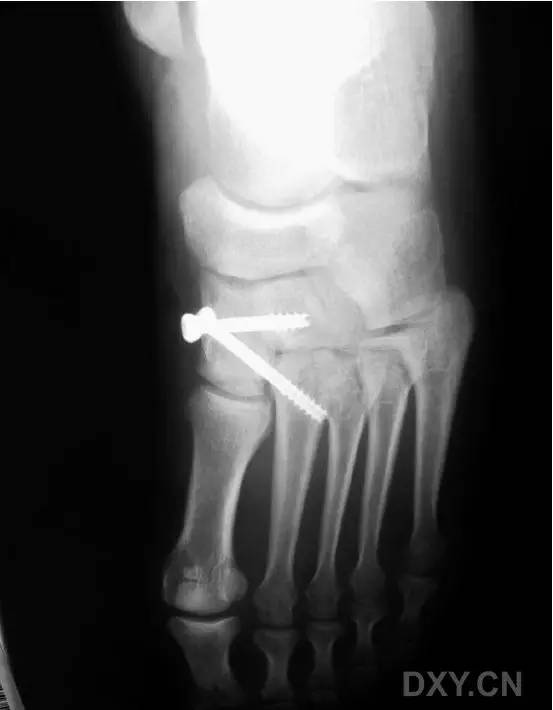

这一损伤的传统固定方式是将 1 枚螺钉(以下简称为 Lisfranc 螺钉)经内侧楔骨向第 2 跖骨基底置入(图 1)。

图 1. 传统的 Lisfranc 螺钉置入方法